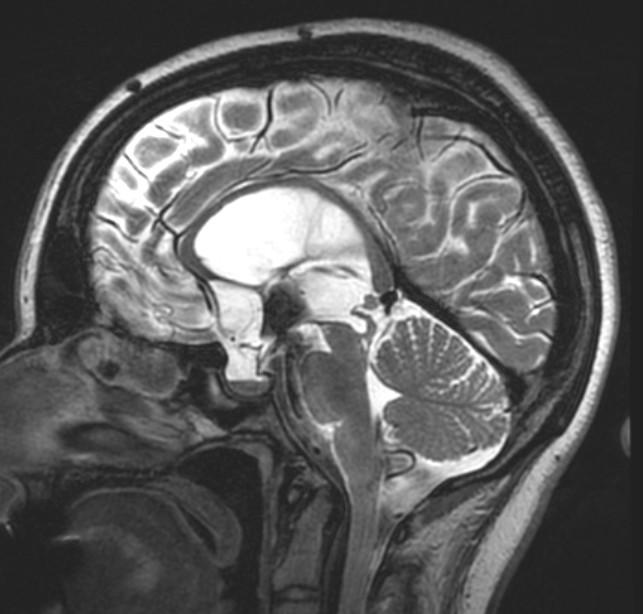

Differential for “cyst in the posterior fossa” starts with whether the vermis is normal or not.

Is the vermis normal? Can you identify the normal structures of the Vermis?

Malrotated hypoplastic vermis, with vertical primary fissure.

“OPEN” fastigial point of the fourth ventricle. Hypoplastic cerebellar hemispheres.

Enlarged posterior fossa

Cystic dilatation 4th ventricle

Uplifted tentorium, TSV sinus, torcula

“torcula-lambdoid inversion” with torcula above the lambdoid suture

Agenetic or hypogenetic vermis with “vermian tail, pushed upward

Cerebellar hypoplasia

CC anomalies 32%

Hydrocephalus up to 90%

Aqueductal stenosis

4th ventricle outlet obstruction

Polymicrogyria, heteropia 5-10%

Occipital Meningo-Encephaloceles 16%

Syndromic = Extracranial anomalies 50%